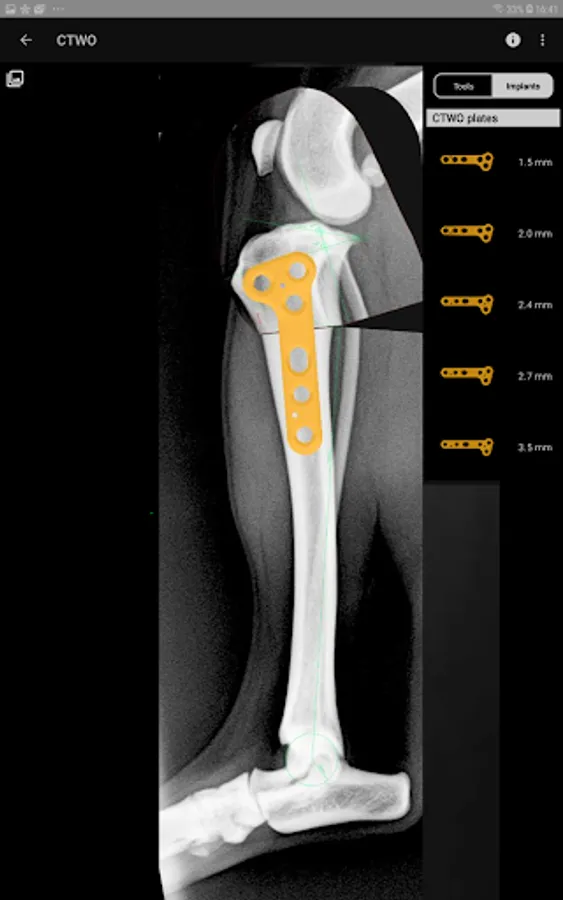

4. Catalogue of BETA Implants locking plates, in 2.0, 2.4, 2.7 and 3.5 sizes:

l) CTWO plates